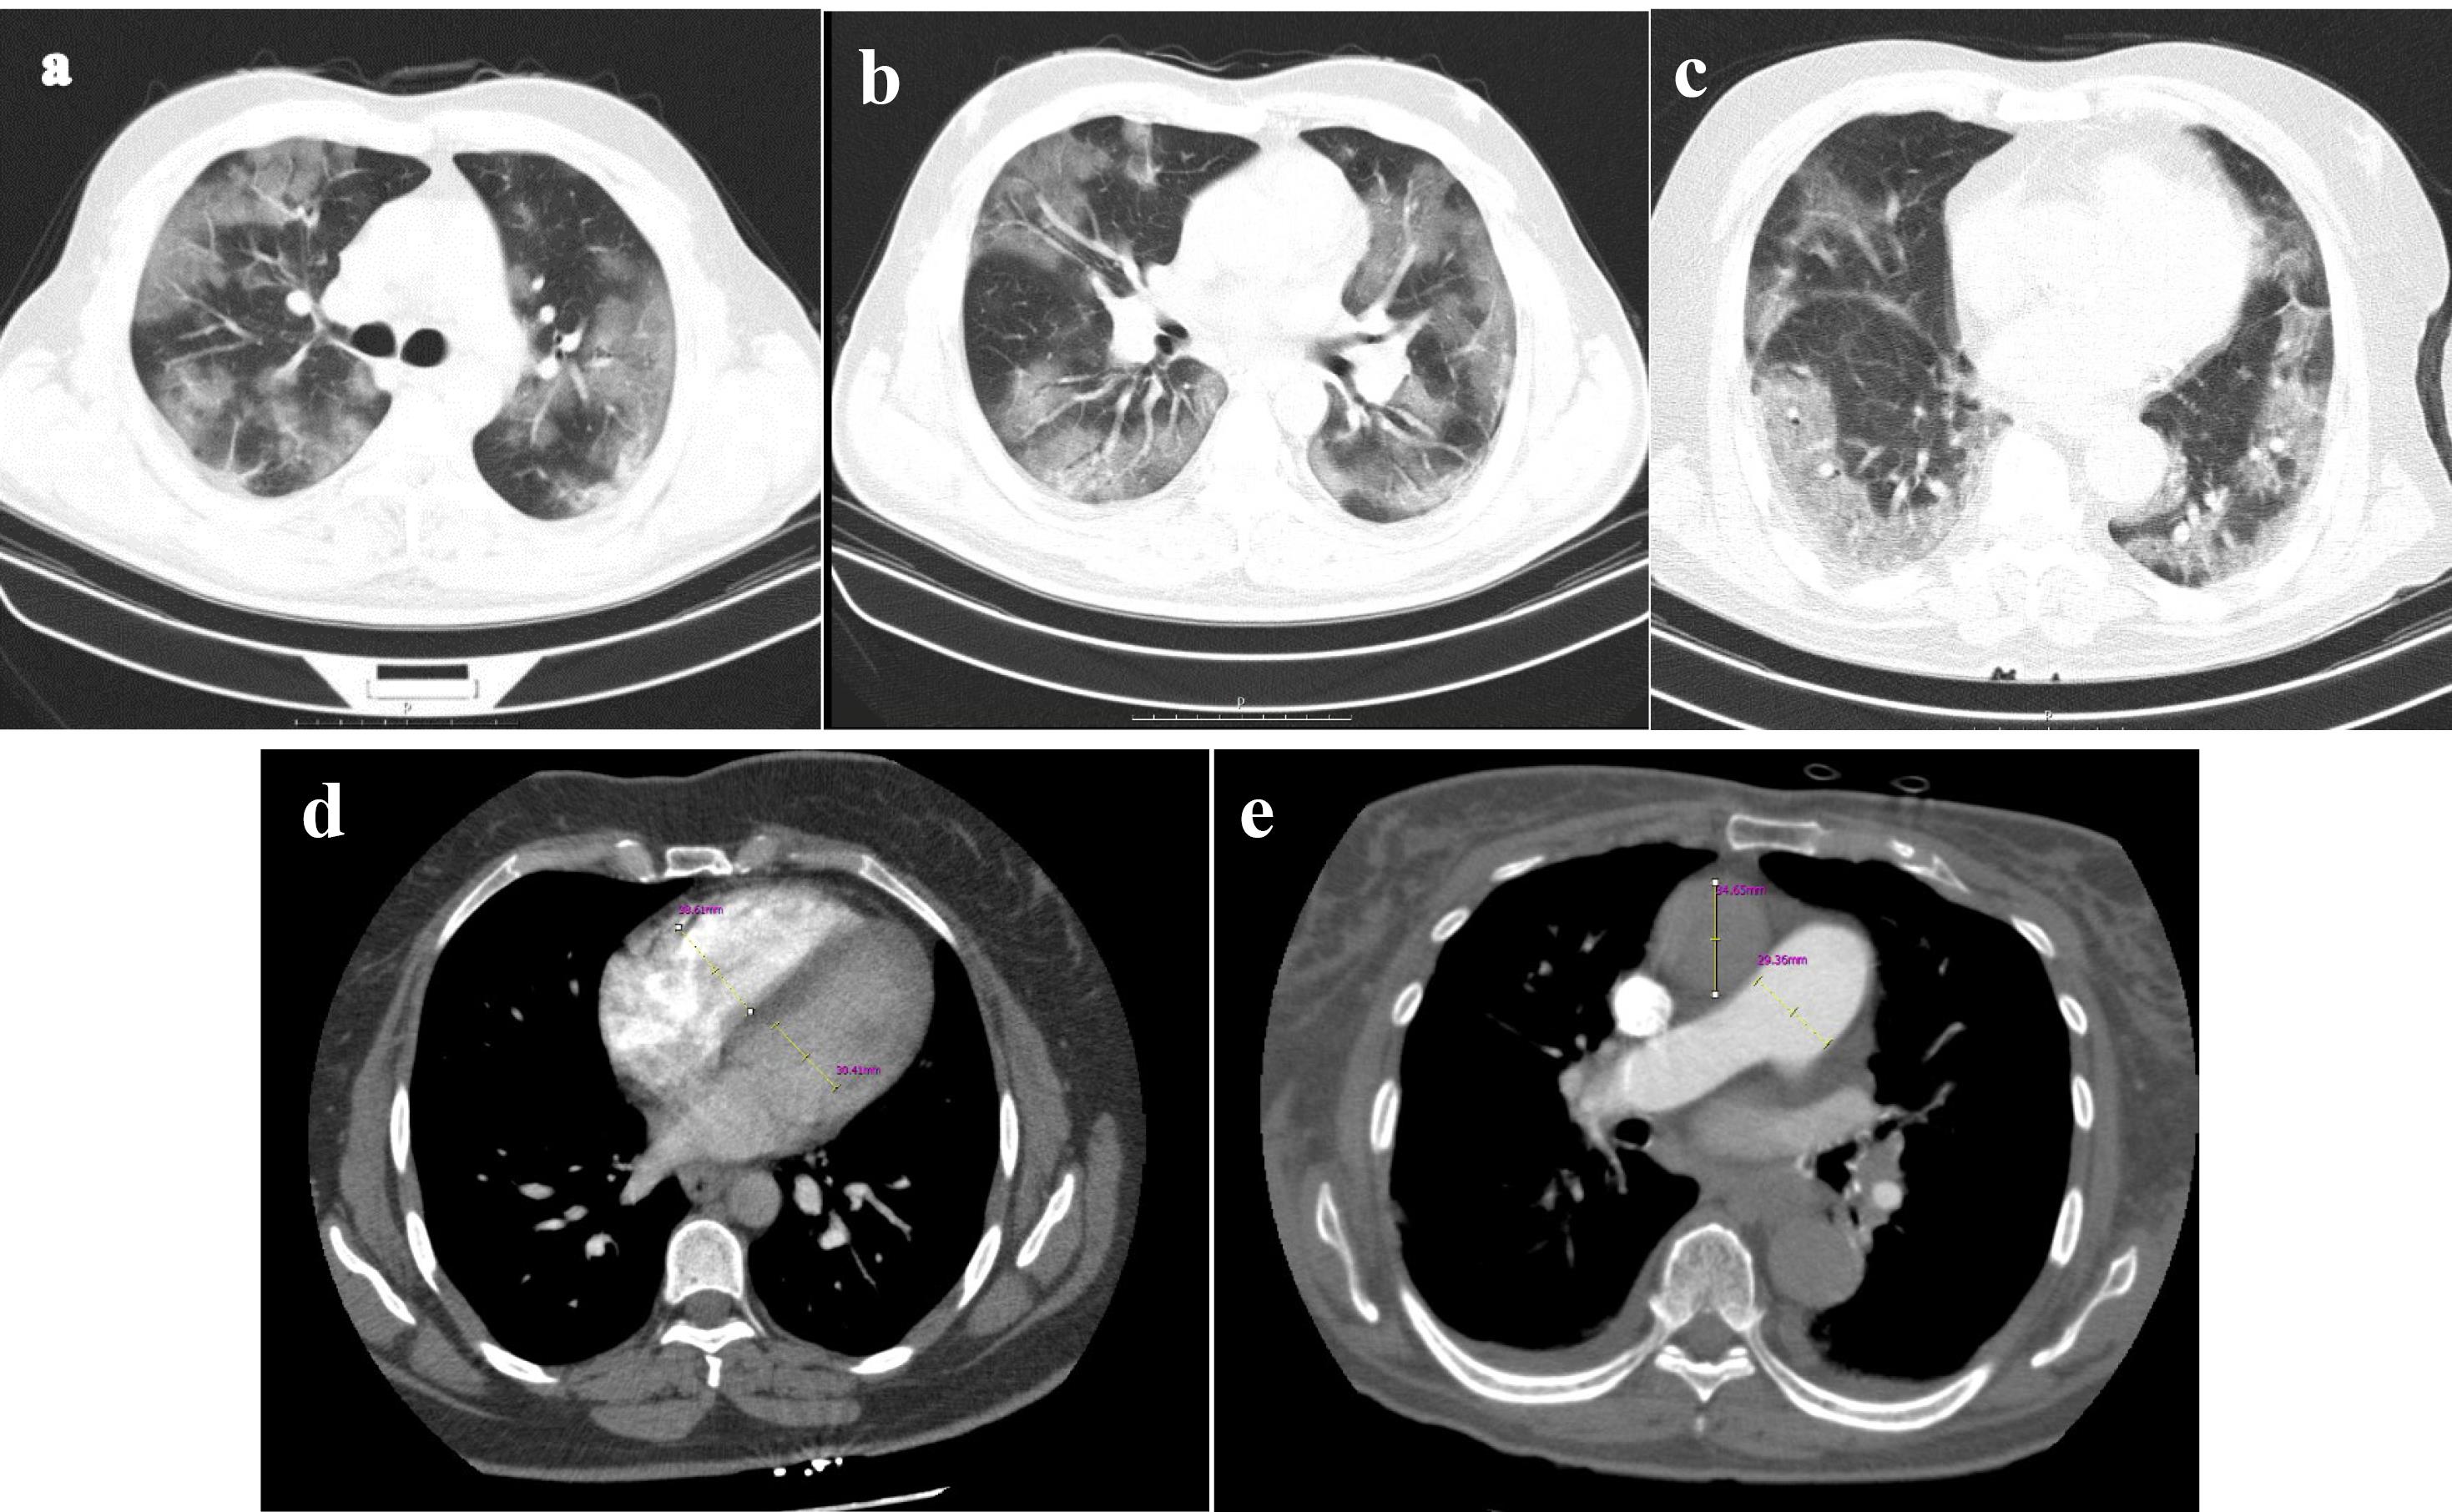

Chamber quantification on CT images

Our cases were scanned by a multidetector CT scanner (Brilliance 64, Philips Medical System, Cleveland, OH, USA). Our CT protocol is as follows: spiral pulmonary computed tomography angiography (CTA), head first supine, caudocranial scan, scan length: 450mm, tube voltage: 120kV, tube current: 350-450mA (adjusted based on the size of patient), slice thickness: 1mm. The pulmonary CTA was performed with an IV injection of 100cc contrast agent (Iodixanol 320 mg/ml). Using the radiology workstation (extended brilliance workspace, Philips Medical Systems Nederland B.V.), the maximum transverse diameter of the right and left ventricles measured just below the level of mitral and tricuspid valves, respectively, in a 4-chamber view, as well as the maximum transverse diameters of the pulmonary artery and the ascending aorta in the axial plane, were retrospectively examined by an expert cardiothoracic radiologist to calculate the exact ratios mentioned in the study (Figure 1).

Aquantitative assessment of pulmonary parenchymal involvement was conducted based on lung window images derived from pulmonary CTA. The scoring for parenchymal involvement in this patient is detailed as follows: Right Upper Lobe (RUL): 11, Right Middle Lobe (RML): 4, Right Lower Lobe (RLL): 14, Left Upper Lobe (LUL): 8, Lingula: 6, Left Lower Lobe (LLL): 14, resulting in a total score of 54 out of 190 (28.42%) (figures a, b, and c). Additionally, the computed tomography angiography (CTA) provided quantitative measurements for the right ventricle (RV) with a diameter of 38mm, left ventricle (LV) with a diameter of 30mm, ascending aorta (AO) with a diameter of 34mm, and pulmonary artery (PA) with a diameter of 29mm (figures d and e). CTA computerized tomography angiography, RV right ventricle, LV left ventricle, PA pulmonary artery, AO ascending aorta

Chest CT severity score

The modified CT scoring system introduced by Yang et al evaluated the percentage of parenchymal involvement in all lung regions (Figure 1).14 To determine the involvement score of each segment, the following criteria apply: 0% is designated as score 0, 1-5% is given score 1, 6-25% is assigned score 2, 26-50% receives score 3, 51-75% is associated with score 4, and 76-100% is attributed a score of 5. Coefficient 1 was used for ground glass infiltration, and Coefficient 2 for consolidation. These mentioned coefficients were multiplied by the involvement score of each lung segment to determine the severity score of involvement in each lung segment. The total CT severity score (CT-SS) will be the sum of the severity score of involvement in each segment. A radiologist reviewed and reported CT findings blinded to patients’ baseline features and laboratory findings.